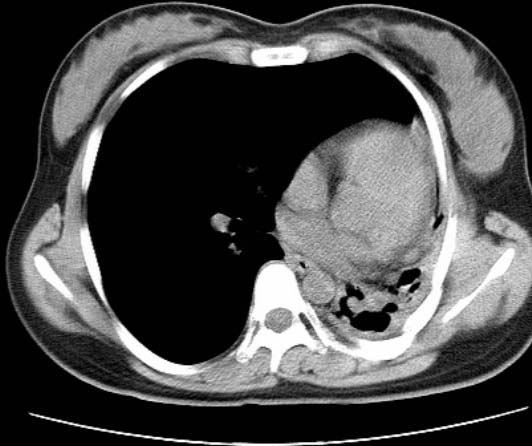

标题: CT25648:求教:是肺发育不全还是结核?

女  20岁。一月前咳血,诊“肺结核”抗痨治疗一月后,咳血停止,现复查。病人精神好。前后ct片对比未见明显变化。既往体检“正常”

1)考虑左肺结核并肺不张、支气管扩张。2)纵隔疝。

考虑左肺结核,左肺毁损,纵膈左偏,既往体检正常不可靠,tb一个月也不会这个样子的,有钙化,应该病程较长,冰冻三尺非一日之寒!

左肺发育不全。

考虑左肺结核,左肺毁损,纵膈左偏,既往体检正常不可靠,tb一个月也不会这个样子的,有钙化,应该病程较长,冰冻三尺非一日之寒

结核,左肺毁损。